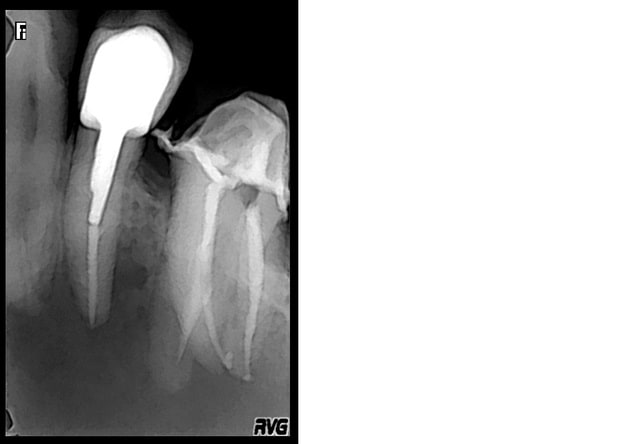

Puis le 08/12/14 je fais la dépose, le rte sous digue. je n'arrive pas à trouver de MV2, ni à aller jusqu'à l'apex de la racine palatine. j'obture., et met un cavit

le 08/12 je fais l'empreinte pour la ccm, prévu à la pose le 15/12.

J'essaye de reprendre le MV2 quand meme: ma lime progresse et je bloque à un moment.

du coup, je fais une radio lime en pace. et là: je crois que je suis dans un faux canal. Moi, les faux canaux, j'arrive jamais à les passer. j'obuture donc là ou je juis après avoir bien irrigué.

Pr  op w1yhiu - Eugenol

Post op yoe5nw - Eugenol

Mv2 wva7f5 - Eugenol

Post op 2 outjqc - Eugenol